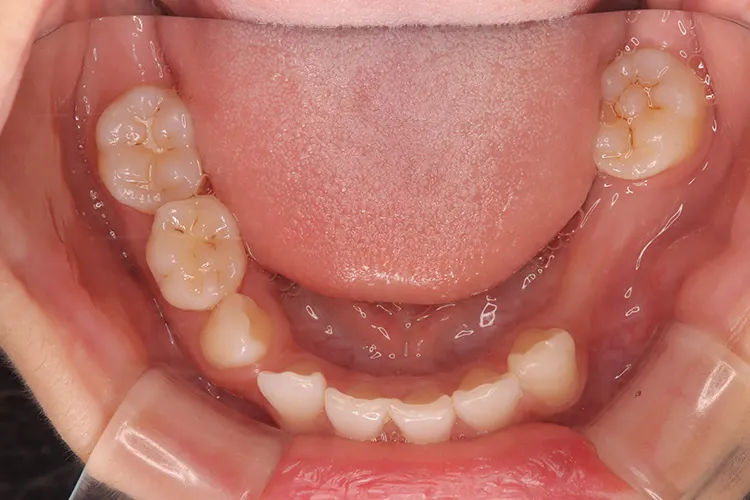

左下の大臼歯の欠損を長期間放置したために上の歯が下がってきてしまい、他の歯医者で被せを入れることができないと断られうちに来られました。下がってきてしまった上の奥歯を部分矯正で上に引っ張り上げ、下に被せ物を入れるスペースを作り、インプラントを入れて噛み合わせを回復しました。部分矯正開始から1年半で治療完了しました。

左下67 欠損に対してインプラント治療を行った症例

部分床義歯を使用していたが、どうしても慣れない上にしっかり噛むことができないためインプラント治療を希望